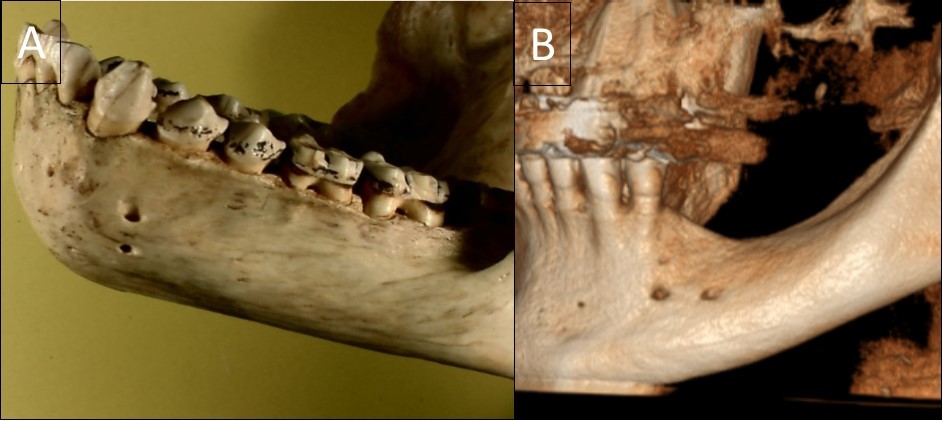

The typical images from modern human and great apes with different anatomical features were shown in Figure 1 and Figure 2. A group of variables were categorized as: the presence of the incisive canal, the number of mandibular canal bifurcations, the potential occurrence of an anterior loop, the presence of the incisive canals, its end-point and connection of the incisive to the lingual canals (Figure 3). Interspecific variability was determined by comparing contemporary human and great ape mandibles. In this analysis, mandibles from the different geographical locations were grouped in the human group, and then compared to mandibles of chimpanzees and gorillas.

Figure 2.A general view of a gorilla mandible with a vertical double foramen (A) and a human mandible with a horizontal double foramen (B).